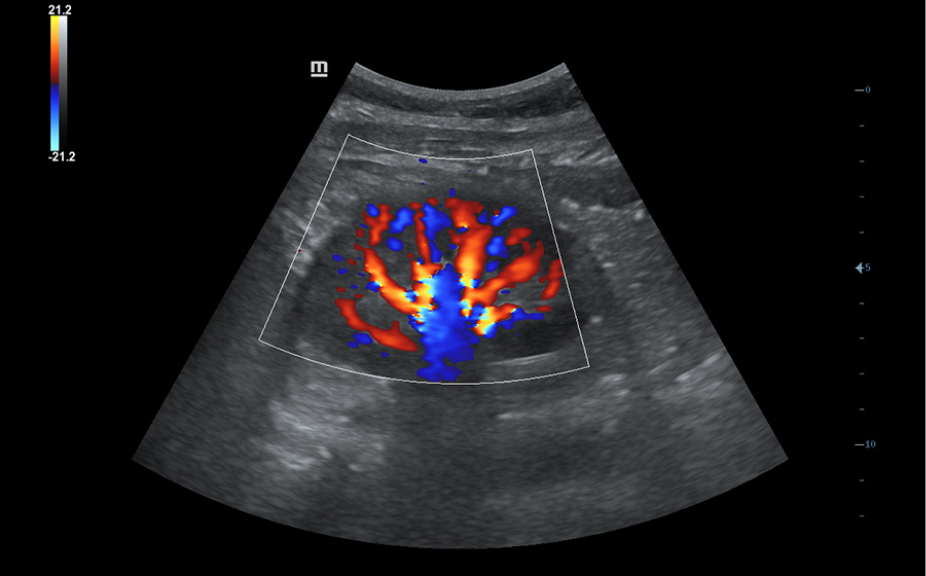

Включает различные режимы визуализации.

Включает различные режимы визуализации.